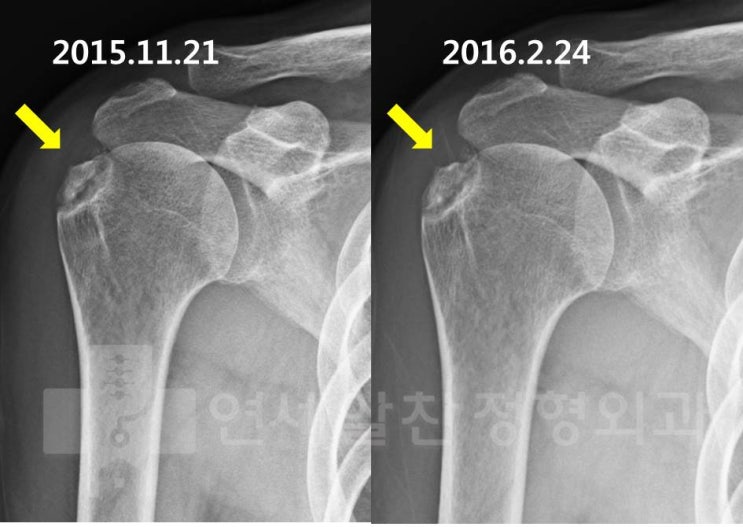

석회성 건염에서 관절경하 석회 제거술의 결과

61세 여자 환자로 좌측 어깨의 극심한 통증을 주소로 내원하였다. 환자는 타병원에서 석회성 건염을 진단 ...

거대한 석회성건염 에서 석회 흡입주사 및 충격파 치료의 효과 및 결과

55세 여자환자로 약 5년간의 어깨 통증을 격어 왔다. 최근 통증이 극심하게 심해지면서 내원하게 되었다. ...